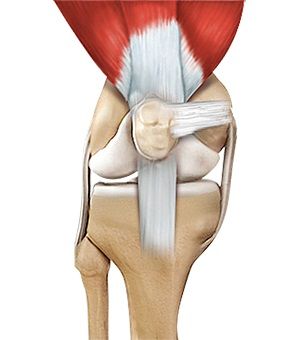

• Quadriceps Tendon

Quadriceps Tendon

Quadriceps tendon is a thick tissue located at the top of the kneecap. The quadriceps tendon works together...